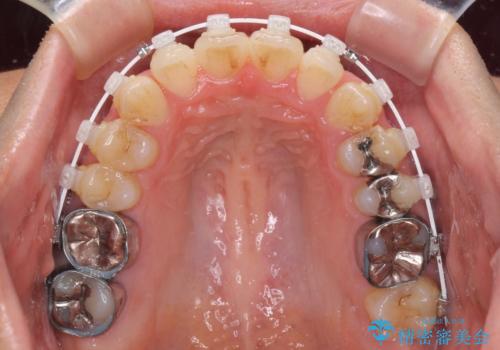

上顎奥歯付近にアンカースクリューを用い、上顎歯列全体の後方移動と、大臼歯圧下を促し、前歯の上下関係を改善することとしました。

奥歯には目立つ銀歯が多くあるので、矯正治療後には下顎の銀歯をセラミッククラウンやセラミックインレーにより、補綴・修復治療することとしました。